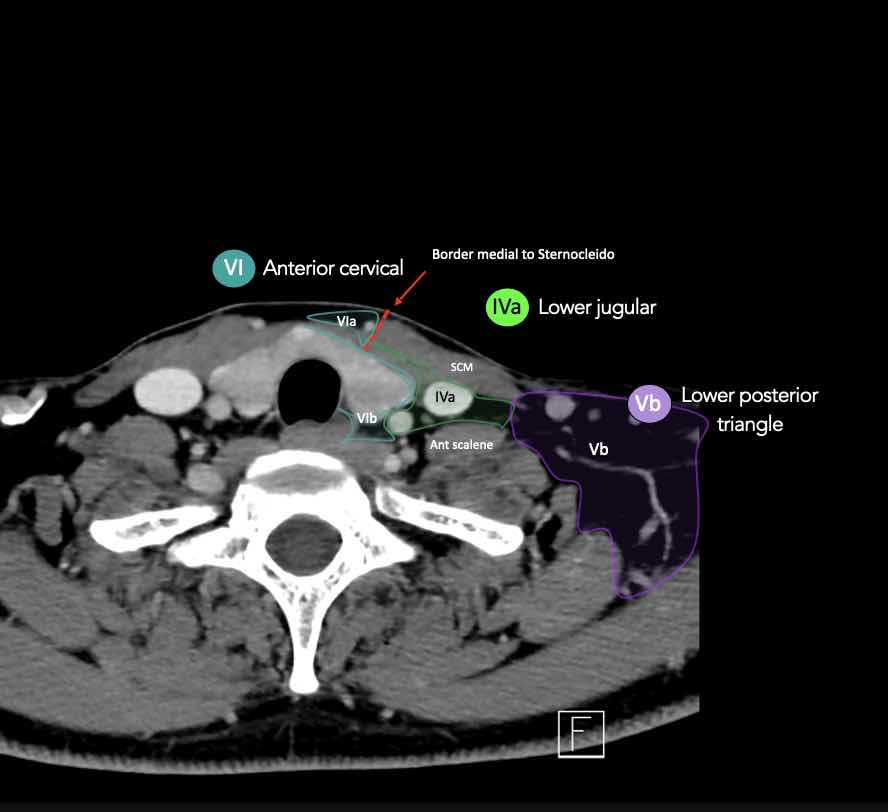

CT Scan Mặt Cắt Ngang (Axial CT)

Các lát cắt CT mặt phẳng ngang tương ứng với hình minh họa tổng quan.

Các lát cắt CT mặt phẳng ngang với hình ảnh chi tiết hơn.

Nhấp vào hình ảnh để phóng to.

VI – Cổ trước

Tầng này chứa các hạch tĩnh mạch cảnh trước nông (tầng VIa) và các hạch sâu hơn bao gồm hạch trước thanh quản, trước khí quản, cạnh khí quản và hạch thần kinh thanh quản quặt ngược (tầng VIb).